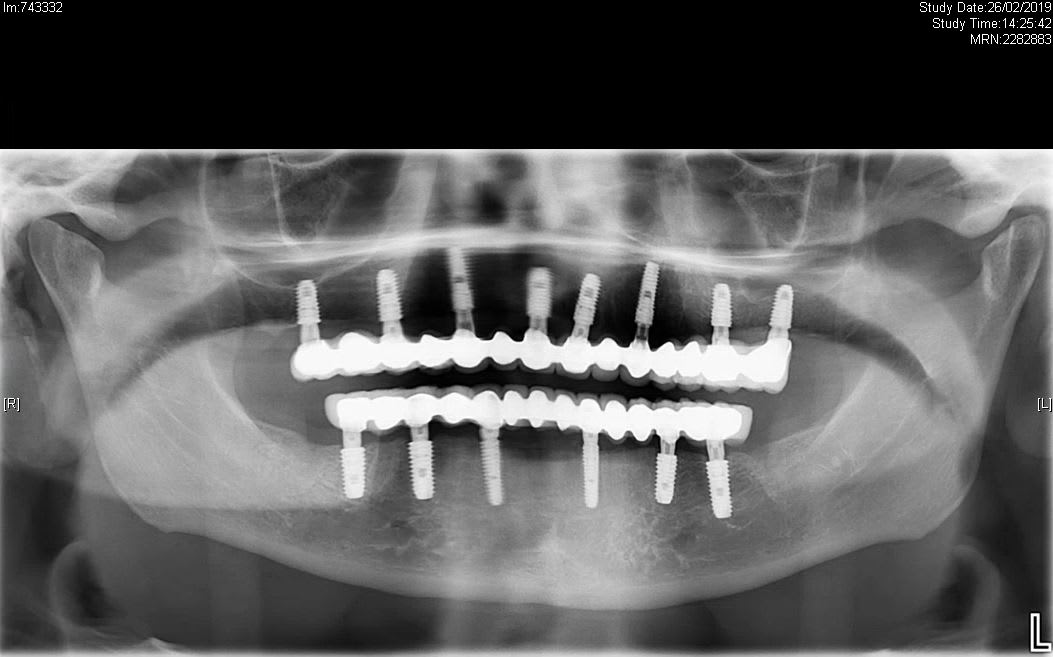

Ensuite..... Plein d'implants... Pas réussi à bien voir en haut en antérieur.... Plus d'os ou image bof ?

Quoi qu'il en soit et surtout en bas je vois pas pourquoi 6 mois plus tard le patient se retrouve edenté complet....

Pour les implants en antérieur, c'est juste une image bof, j'ai des rétro-alvéolaires qui montrent que tout va bien.

2ème RDV en Février 2019, nous apprenons que la patiente s'est faite poser des implants en Turquie (ne me demandez pas pourquoi, mais çà sent le deuxième épisode de surtraitement, soit elle est volontaire, soit naïve et pas de bol, je ne sais pas, c'est sa fille qui traduisait je n'ai pas insisté) en Aout 2018, et souffre depuis de douleurs permanentes, irradiantes dans toute l'hémiface droite, jusque dans le cou, l'épaule et le sommet du crâne. Nous ne diagnostiquons aucun défaut implantaire ni pathologie en bouche.